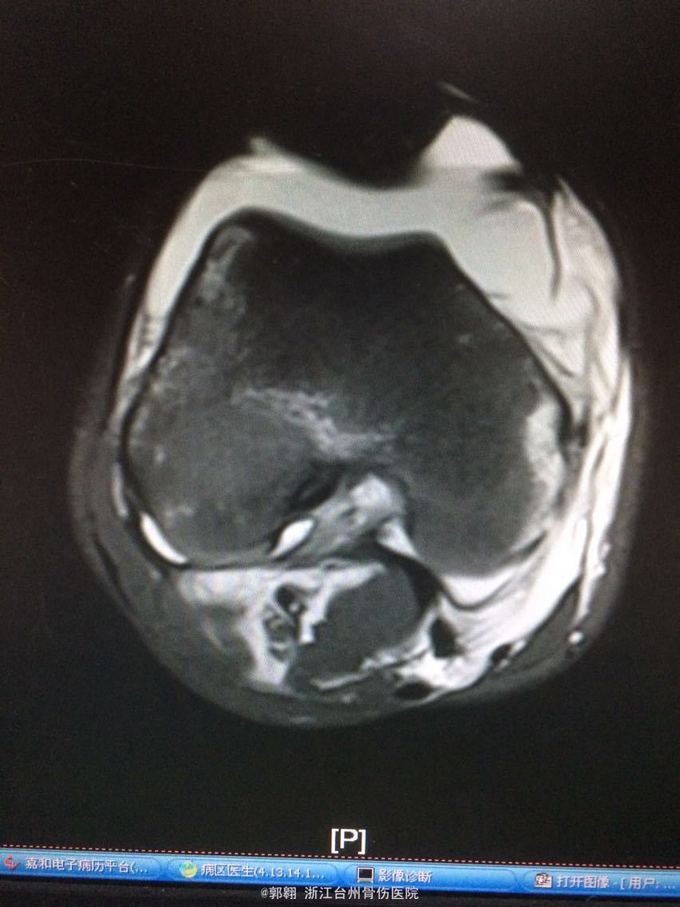

右膝关节跑步摔伤疼痛功能障碍3小时 病史:患者15岁 上体育课时跑步摔倒致右膝关节畸形疼痛 功能障碍,由老师送至医院就诊。

查体:右膝关节及小腿上段肿胀明显,张力较大,压痛位于内侧副韧带股骨处和膝关节外侧,膝关节波动感,浮髌试验阳性、扳膝试验阳性、抽屉试验阳性、Lachman阳性、膝关节屈伸活动因疼痛而障碍,足背动脉波动良好。 MRI:右膝关节股骨内髁骨折 胫骨平台外侧缘骨折

诊断:右膝关节内侧副韧带撕裂 前交叉韧带损伤 股骨内侧髁骨折胫骨平台外侧缘骨折 腓肠肌肌肉拉伤 处理:制动 支具托固定 冰敷 退肿止血药物治疗